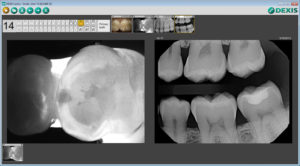

The DEXIS™ CariVu™ caries detection device helps me diagnose caries with great accuracy and without exposing patients to ionizing radiation.

It uses transillumination technology – the image on the screen is similar to that of an X-ray, and the enamel appears transparent while porous lesions appear as dark areas. This is especially helpful for the identification of occlusal, interproximal, and recurrent carious lesions and cracks not visible on other imaging methods.

When a radiolucency on a radiograph is not clear enough for a definitive diagnosis, or if an incipient lesion goes around the interproximal and curves toward the lingual or buccal, a CariVu image offers a big advantage.

Without CariVu, I put a “watch” on that patient’s chart or take an “educated guess” if I see a “darkness” in the interproximal area of the tooth. I would rather have a transilluminated image that shows the carious area with a 99% accuracy* rate than take the chance that the caries may reach the pulp before the patient’s next appointment, or infected structure may be lurking beneath a carious lesion. The CariVu image also shows me if a certain spot can, in fact, just be watched and given a course of preventative care before treatment. During cleaning, the reparative dentin can cause staining sometimes mistaken for caries, and CariVu is an efficient double check for that situation as well.

Patients have an easier time identifying a problem on a transilluminated image. My team and I also appreciate that we can get images on children whose small mouths or gag reflexes make radiographs difficult.

CariVu images are captured from the portable handpiece and go directly into the DEXIS software to be stored with the patient’s intraoral X-rays and camera images.